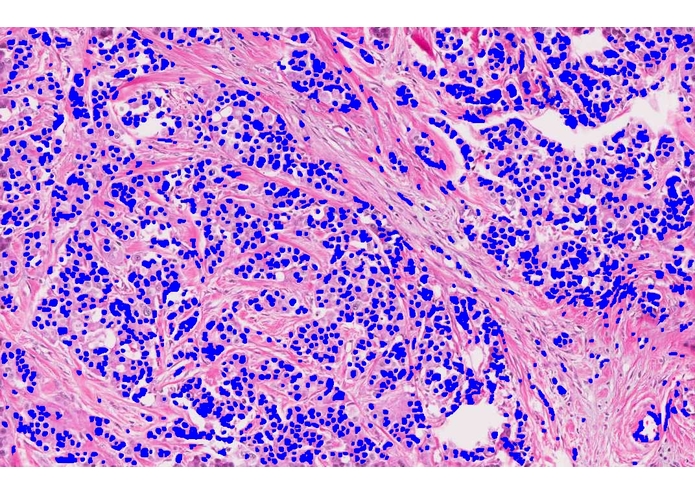

I used support vector machines (SVM) to develop a machine learning model that accurately predicts whether a breast cancer patient is likely to experience a recurrence after treatment. The prognosis method examines the patient's biopsy slide image with computer vision and leverages complex statistical methods to analyze the expression values of thousands of genes.